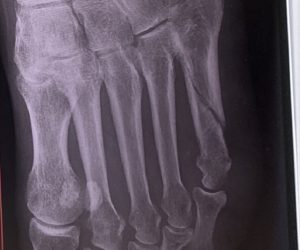

前回は第五中足骨基部骨折、今回は小指側の広い範囲を骨折。

この記事では第5中足骨骨折をした当日から2週間までの様子と、骨折期間中にあると便利だったもの3選を私の骨折した経験を元にまとめています。

記事中骨折した箇所の画像も掲載しています。少しでも参考になれば幸いです。

12年ぶりに骨折。前回は第五中足骨基部骨折で今回は第五中足骨(足の甲の小指側)を骨折しました。

レントゲン撮って折れているのを確認したらすぐにギブスとなりました。

まぁ普通に斜めボッキリに折れていたので骨がズレないように固定するのは仕方ないか。

この日は2回めの診察で、レントゲンを撮りました。

見せられた画像では斜めに折れた骨がほんの少しズレていたが、許容範囲と先生に言われました。

折れた場所にもよるのだろうけれど、関節ではなく小指から伸びる骨が折れているのでこの程度のズレは大丈夫なのだろう、と勝手に考える。

今回もレントゲンを撮って骨折部分のズレを確認し、許容範囲だといわれました。許容範囲という言葉がこれほどまでに幸せに感じるのも、骨折しているメンタルのせいか。